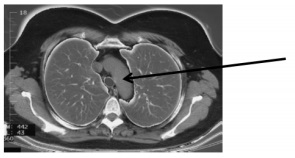

Qual é o ponto assinalado pela seta na imagem de tomografia a seguir?